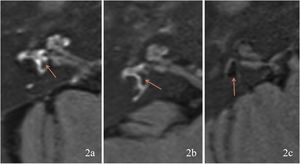

Evaluation of EHThe MRI results were classified according to the degree of EH using the criteria described by Gürkov et al.8 in 2011. Four scales were used for cochlear EH: Scale 0 (none hydrops, no enlargement of the endolymphatic space is noted in the cochlea and vestibule, and the perilymphatic space is clearly visible) (Fig. 1a); Scale 1 (mild hydrops, the endolymphatic space is enlarged with hypointensity bulging into the perilymphatic space with hyperintensity) (Fig. 1b); Scale 2 (marked hydrops, the endolymphatic space is enlarged, the scala media is convex to the scala vestibuli, and the perilymphatic space is semicircular) (Fig. 1c); and Scale 3 (extreme hydrops, the endolymphatic space is severely dilated, the scala media continues to be convex to the scala vestibuli, and the perilymphatic space is compressed into a flattened line) (Fig. 1d). Vestibular EH was classified into three degrees by calculating the ratio of the area of the endolymphatic space to the total area of the endolymphatic and perilymphatic spaces (R-value), with R ≤ 1/3 for Grade 0 (no hydrops) (Fig. 2a), 1/3 < R < 1/2 for Grade 1 (mild hydrops) (Fig. 2b), and R ≥ 1/2 for Grade 2 (significant hydrops) (Fig. 2c). All imaging results were evaluated by two specialized radiologists. Inconsistent results were resolved by consulting a senior radiologist.